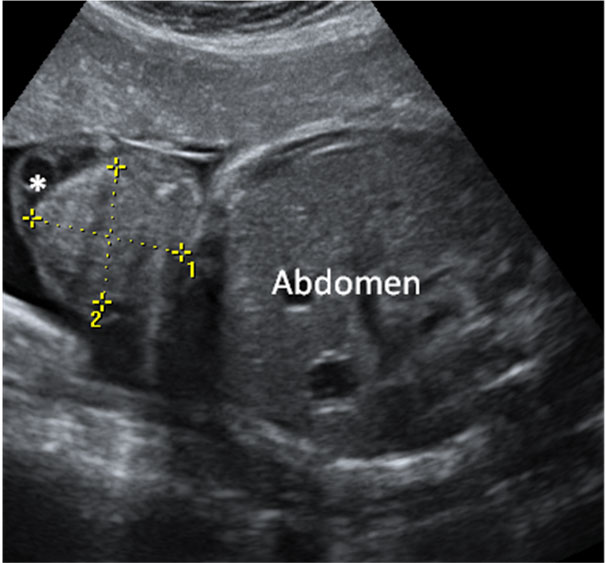

En esta imagen obtenida con una ecografía en 4D de un feto de 20 semanas de gestación se contempla cómo el bebé mueve sus brazos delante de su cara. Aún se encuentra muy delgado, ya que es a partir del tercer trimestre, sobre todo, cuando el feto empieza a acumular grasa bajo su piel.

Ecografía de bebé de 20 semanas de perfil

Podemos ver claramente los miembros superiores: el feto flexiona los brazos y los pasa por delante de la cara